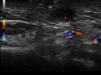

Varón de 32 años de edad, sin antecedentes médicos de interés, que acudió a consulta de dermatología por presentar un tumor en forma de cuerno cutáneo engastado en la piel, situado en la rama horizontal mandibular izquierda (fig. 1). En la exploración de la cavidad oral no se apreciaron alteraciones. Refería dolor a la palpación en esa zona. Había realizado tratamiento con pomada tópica de mupirocina 2% sin notar mejoría. Se realizó ecografía cutánea en modo B (Esaote®, Génova, Italia, sonda 18MHz) donde pudimos observar una estructura hipoecogénica en banda, algo tortuosa y medianamente delimitada que alcanza la superficie de la cortical ósea mandibular (fig. 2). El estudio mediante modo doppler mostró vascularización en la zona circundante a dicho trayecto, revelando signos inflamatorios que se complementaban con un contorno hipoecogénico mal definido en modo B (fig. 3). Con el diagnóstico de fístula dentocutánea el paciente fue derivado al servicio de cirugía maxilofacial, donde se completó el estudio con una ortopantomografía, detectándose una imagen radiolúcida apical que englobaba la raíz posterior del primer molar izquierdo (fig. 4). Se realizó tratamiento conservador mediante endodoncia y restauración, con una obturación de amalgama, curando la fístula cutánea en 20 días.

Recientemente Shobatake et al. han publicado 3 casos de fístulas dentocutáneas diagnosticadas por ecografía5. La ecografía dermatológica muestra un trayecto fistuloso hipoecogénico en banda, algo tortuoso y medianamente delimitado que alcanza la superficie de la cortical ósea con mayor o menor vascularización en el modo doppler, siendo un patrón sonográfico bien definido. Es una herramienta que complementa con rapidez otras técnicas radiológicas, y se presenta como una excelente opción para facilitar el diagnóstico de este tipo de lesiones, incluso en dermatólogos no especialmente diestros en el manejo de la enfermedad oral. Además, posibilita la monitorización terapéutica y la valoración de la probable inflamación asociada, para facilitar una posible profilaxis antibiótica previa a la intervención.